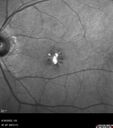

74 year old female: Seeing "Diamonds in central vision" when first waking up OU. Duration of Problem: about 6 weeks. Location: central vision. Modifying Factors: Lasts just a few minutes. Medical Hx: Cancer (Breast). Surgical Hx: Lumpectomy. Appendectomy. nose surgery. Systemic Meds: Ibrance. Faslodex. Zomita. Vitamin D3. VA OD: Dsc20/40+2 VA OS: Dsc20/50+1 IOP: TP: OD:18 OS:21

Pattern Dystrophy with Collapsed Vitelliform39 views74 year old female with vision loss in eye with collapsed vitelliform lesion.00000